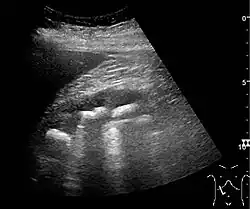

With US, larger stones (>5–7 mm) within the kidney, i.e., in the calyces, the pelvis and the pyeloureteric junction, can be differentiated, especially in the cases with accompanying hydronephrosis (Figure 18 and Figure 19). Hyperechoic stones are seen with accompanying posterior shadowing. Additional twinkling artifacts below the stone can often be seen using Doppler US. Large stones filling the entire collecting system are called coral stones or staghorn calculi and are easily visualized with US (Figure 20). Stones in the ureters are usually not visualized with US due to the air-filled intestines obscuring the insonation window. However, ureteral stones near the ostium can be visualized with a scan position over the bladder. An exam of the ureteric orifices and the excretion of urine to the bladder can be performed by inspecting the ureteric jets in the bladder with color Doppler US.

Figure 20. Staghorn calculi filling the entire collecting system and creating pronounced shadowing.[1] -